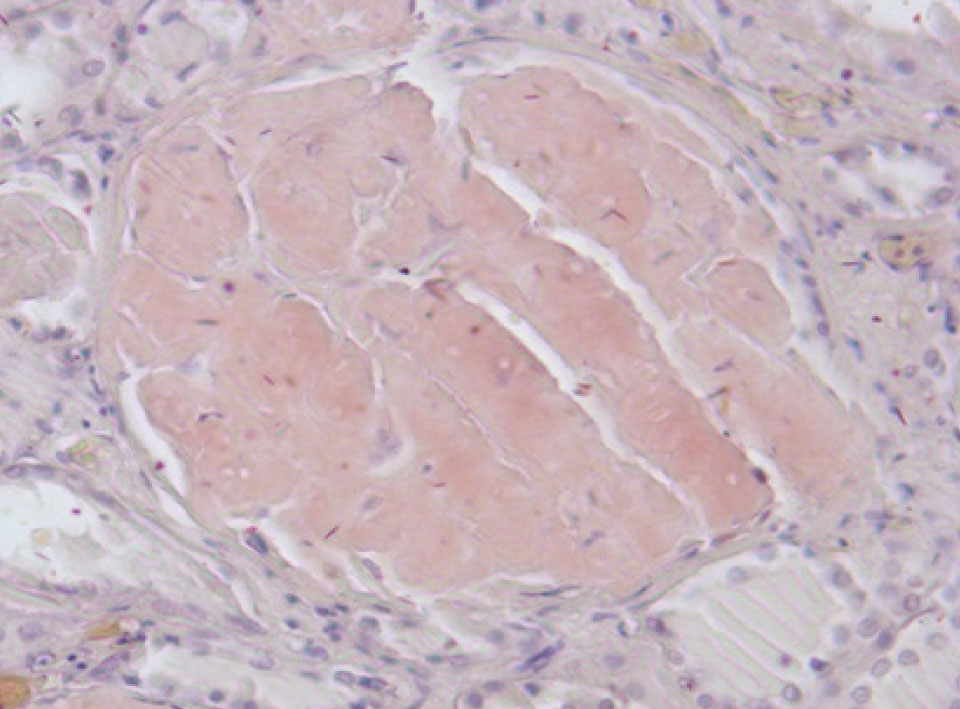

Рис. 2. Амилоид в красной пульпе селезёнки. Окраска конго красный, ×200

Гистологическое исследование. Сердце – кардиомиоциты гипертрофированы, диффузный кардиосклероз. При окраске на амилоид в строме и стенке сосудов отложение амилоидных масс (рис. 1). Селезенка – красная пульпа полностью замещена однородными массами, дающими положительную окраску на амилоид (рис. 2).